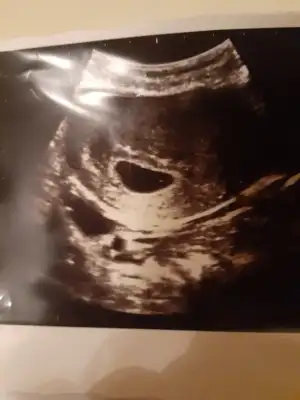

Iütfen yardim edin. Cinsiyet tahmini yaparmisiniz 6 haftalık bir görüntü.şimdi 9 olduk

20,2 KB · Görüntüleme: 129